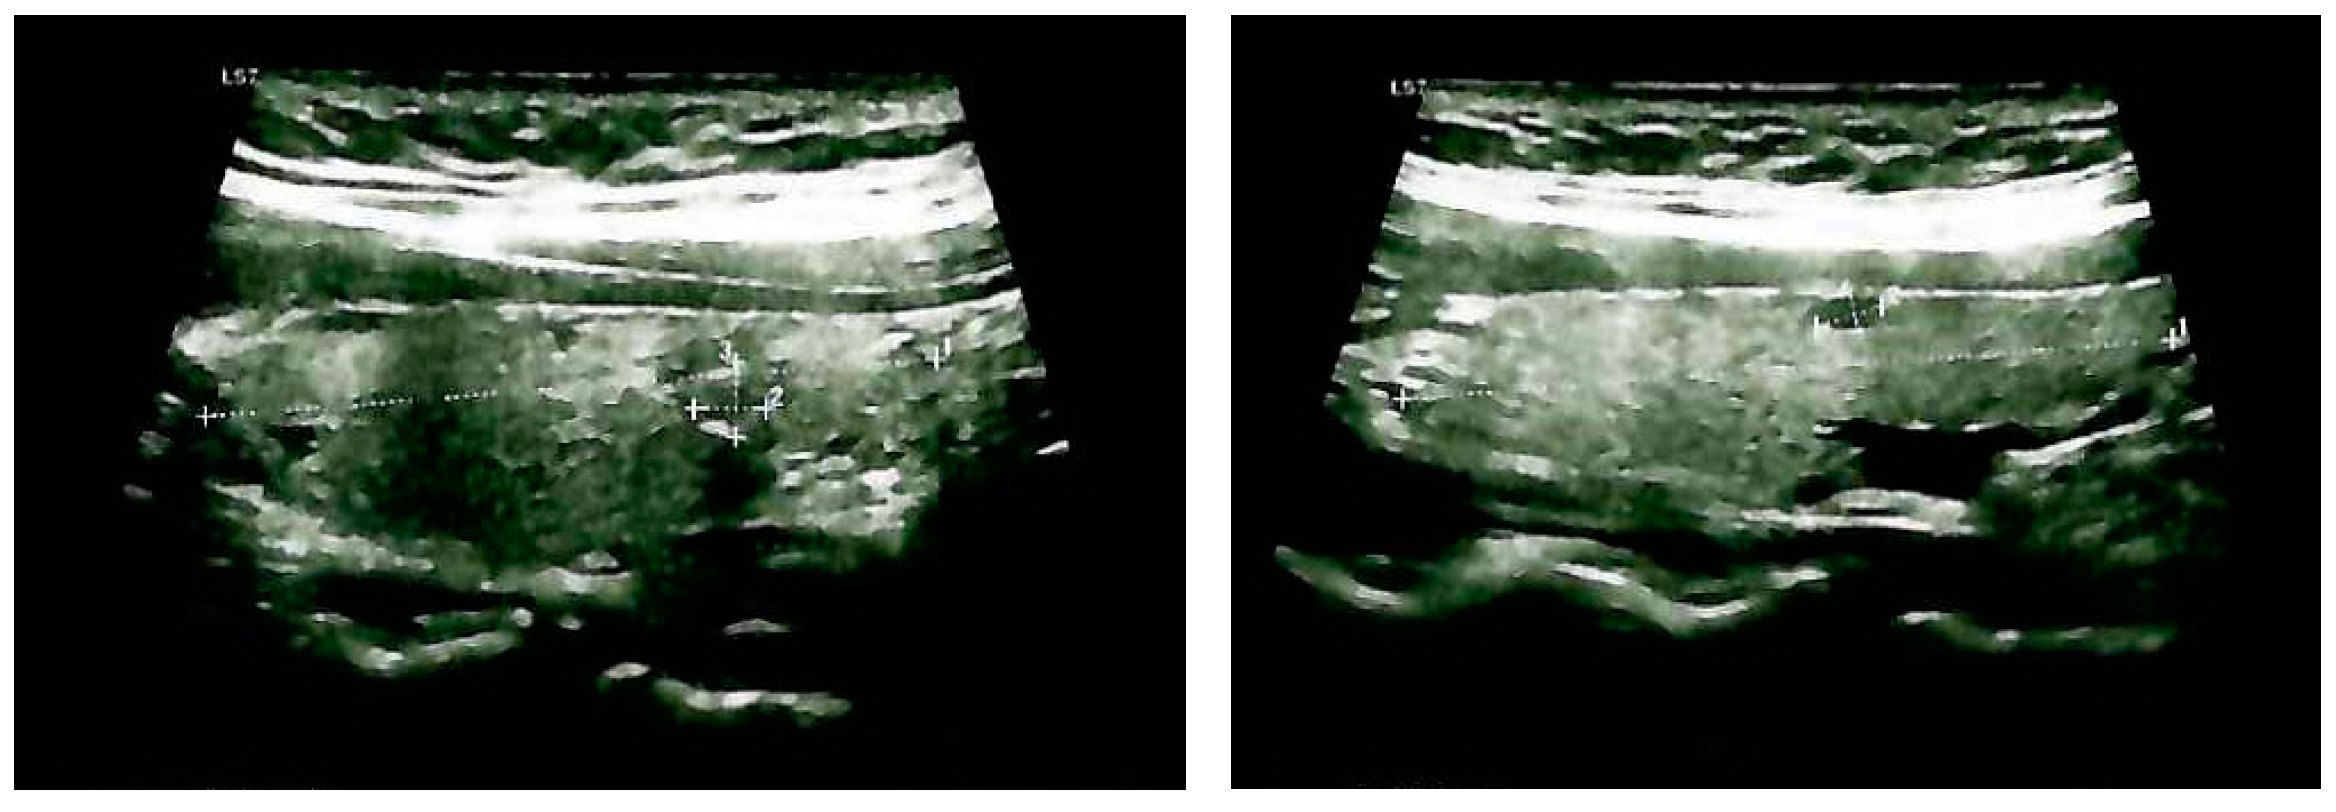

3.1.2. Endocrine and Imaging Investigations After One Year of Surveillance

3.1.3. Ectopic Mediastinal Thyroid Tissue: 99m-Tc Scintigraphy Exploration